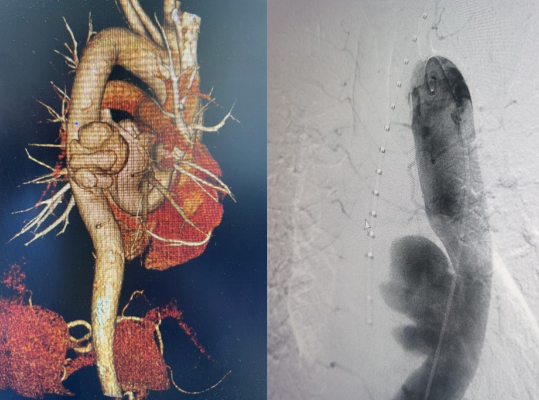

近日,江南在线体育胸心外科收治了一名胸主动脉瘤患者。患者58岁,男性,6月前出现腰背部疼痛不适,症状持续不缓解,多次就诊于当地医院。完善相关检查未见明显异常,给与止痛药物口服对症治疗,症状较前稍缓解。期间,上述症状间断发生。2周前,患者腰背部疼痛转移到胸背部疼痛,继而向前胸部扩展,疼痛无法耐受,就诊于市中心医院。入院后,胸主动脉CTA检查提示“胸主动脉瘤”,大小4.5x6.4x6.8cm,破口上下径2.8cm,胸心外科以“胸主动脉瘤”收治进一步治疗。

经过胸心外科、介入科、麻醉手术室、超声科多学科协作,于11月4日下午4点在急诊局麻下行胸主动脉覆膜支架夹腔内隔绝术,术中精准释放覆膜支架,复查血管造影显示,封闭主动脉破裂口,无内漏,支架位置良好,术区相关动脉血管显影良好,“不定时炸弹”成功拆除。术后给予患者抗板、止痛、控制血压等相应治疗,患者目前恢复良好,已顺利出院。该手术的成功,充分体现了我院多学科积极协作的团队精神。